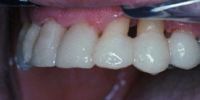

Estético y cómodo, el retenedor de Ribbond está finalizado.

A diferencia de un alambre de metal, Ribbond ofrece una estética superior y no es visible.